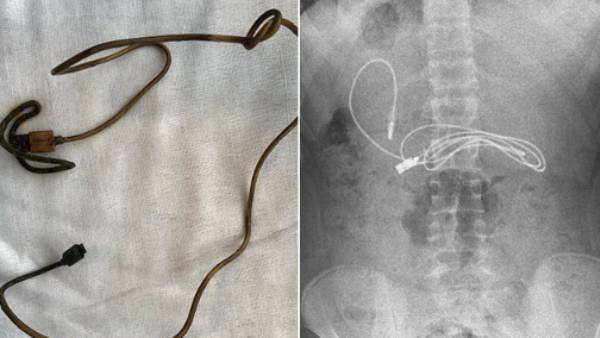

இதை ஏற்றுக்கொண்ட சிறுவனின் பெற்றோரும் எக்ஸ் ரே எடுக்க சம்மத்தித்தனர். இதன் படி எக்ஸ் ரே எடுத்து பார்த்ததில் சிறுவனின் வயிற்றுக்குள் மூன்று அடி நீளத்தில் சார்ஜிங் கேபிள் கிடந்தது மருத்துவர்களை அதிர்ச்சி அடைய வைத்தது. சிறுவனின் வயிற்றுப்பகுதிக்குள் இருந்த சார்ஜிங் கேபிளை உடனடியாக எடுக்க வேண்டும் என்று அறிவுறுத்தினர். இதன் பேரில் அருகில் உள்ள பிரட் பல்கலைக்கழக மருத்துவமனையில் சிறுவன் அனுமதிக்கப்பட்டான்.

அறுவை சிகிச்சை இன்றி வயிற்றுக்குள் இருந்த கேபிளை அகற்ற முடிவு செய்த மருத்துவர்கள் எண்டோஸ்கோபி முறையில் சார்ஜிங் கேபிளை எடுத்தனர். சுமார் 2 மணி நேரம் இந்த சிகிச்சை நடைபெற்றது. சிறுவன் நல்ல உடல் நிலையில் இருந்ததால் உடனடியாக மருத்துவமனையில் இருந்து டிஸ்சார்ஜ் செய்யப்பட்டான். எனினும், சுமார் 1 மீட்டர் நீளம் கொண்ட சார்ஜிங் கேபிளை சிறுவன் தவறுதலாக விழுங்கியிருக்க வாய்ப்பு இல்லை என்பதால் சிறுவனை மன நல மருத்துவரிடம் சிகிச்சைக்கு அனுமதிக்குமாறு பெற்றோர்கள் அறிவுறுத்தினர்.

எண்டோஸ்கோபி மூலமாக சிறுவனின் வயிற்றுக்குள் இருந்த கேபிள் அகற்றுவதில் சிக்கலான மருத்துவ நடைமுறைகள் இருந்ததாக டாக்டர்கள் கூறினர். கேபிளின் ஒரு முனை சிறு குடல் பகுதிக்குள் சென்றதால் எண்டோஸ்கோபி முறையில் அகற்றுவது மிகவும் கடினமானதாக இருந்தது என்று டாக்டர்கள் தெரிவித்தனர். மேலும் சிறுவனின் வயிற்றிற்குள் முடிகளை கட்டும் ரப்பர் பேண்டுகளும் இருந்ததாக மருத்துவர்கள் தரப்பில் கூறப்பட்டுள்ளது.